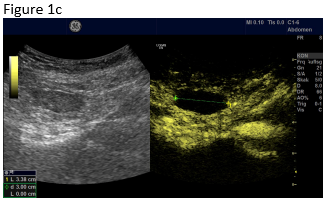

Figure 1: B-mode ultrasound using low frequency (a) and high frequency (b) revealed an isoechoic mass with a hypoechoic circumference. The mass was not adher-ent to the colon. Contrast enhanced ultrasound using low frequency (c) and high frequency (d) revealed that it was a non-enhancing segment of the omentum. Strain elastography showed that the lesion was stiffer than its sur-rounding tissue.